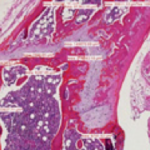

Histomorphometry

Histomorphometric, or digital image, analysis is an important tool in the assessment of many types of histopathology changes. Digital photomicrographs are made and imported into image analysis software. The images are analyzed by the software and appropriate calculations and statistical analysis performed. The following are but a few examples of tissues and tissue disorders in which histomorphometry assessments may be informative: